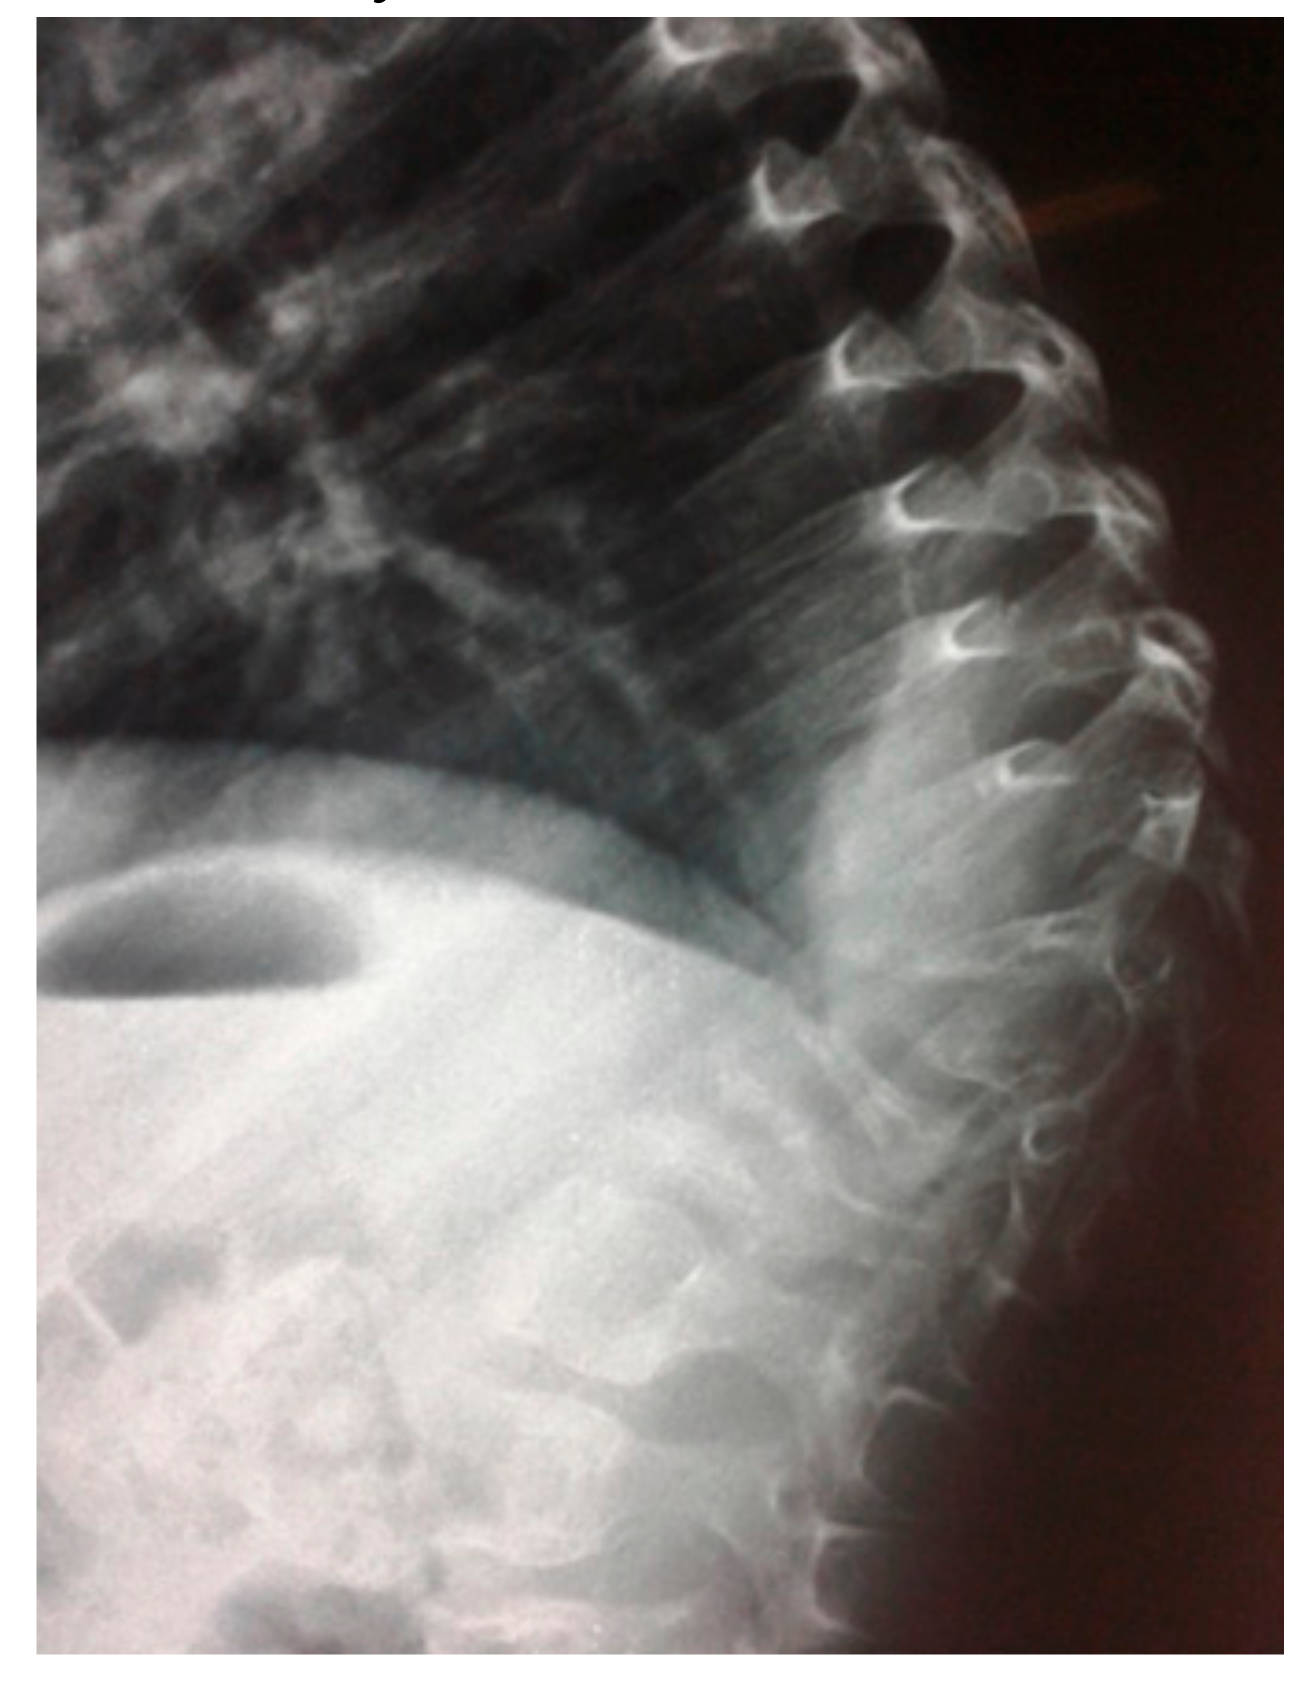

- A ten-year-old-girl presented with painful acute upper thoracic kyphosis. Radiographs of the spine were difficult to assess. 3D reformatted CT scan of the thoracic spine showed progressive osteolysis of T3-T6 (Figure 2). Skeletal survey did not show any other involved areas.